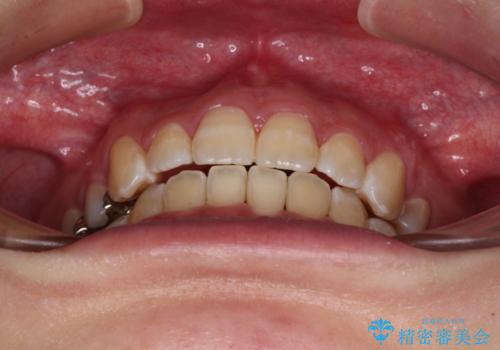

- 八重歯と口の閉じにくさを気にして来院された患者様です。

上下ともに前歯が前方に突出し、八重歯が唇に引っかかる感じもあり、口が閉じにくくなっていました。

上下左右の第一小臼歯4本を抜歯し、口元の突出感を改善しながら八重歯を解消していくこととしました。